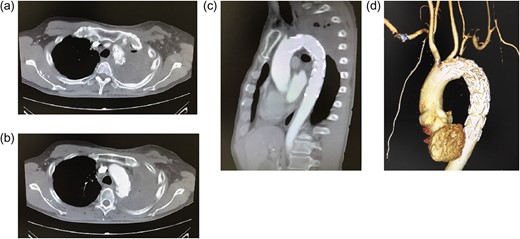

(a–c) Postoperative enhanced computed tomography (CT) (a, b: axial images; c: sagittal image). (d) 3D CT. The aortic rupture is confirmed to be effectively treated. There is no extravasation of contrast medium or endoleak. The origin of the left subclavian artery is occluded. Distal to the occluded site, the subclavian artery is perfused via collateral communications. The left vertebral artery is patent.